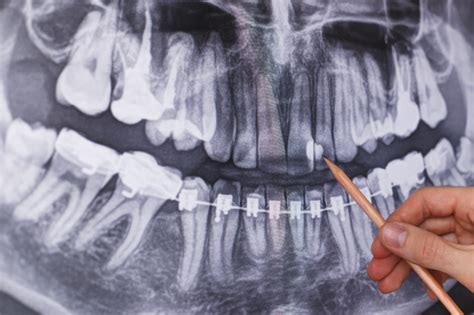

Ejemplo de reabsorción ósea que puede dificultar la colocación de implantes.

El Desafío de la Reabsorción Ósea

El hueso de los maxilares sufre modificaciones a lo largo de los años, lo que puede generar complicaciones para la colocación de implantes dentales. En el pasado, esta situación a menudo implicaba el uso de dentaduras postizas.